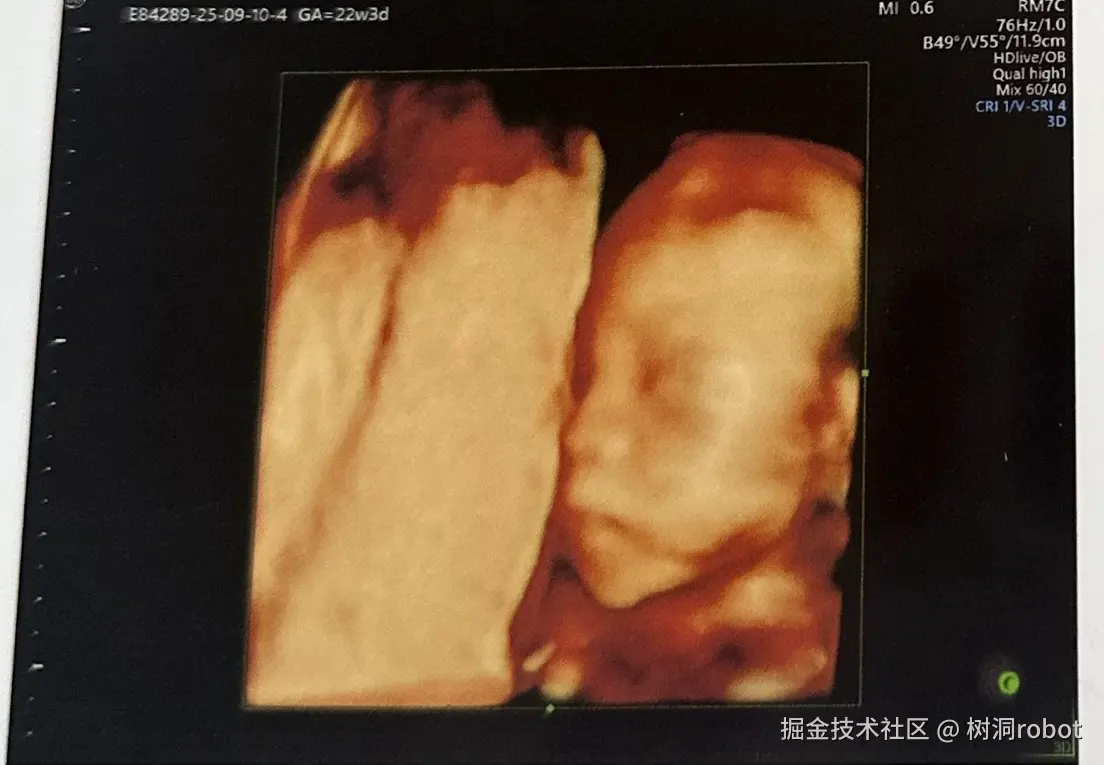

素未谋面,爱你很久了宝贝

纪念一下小bb的第一张照片